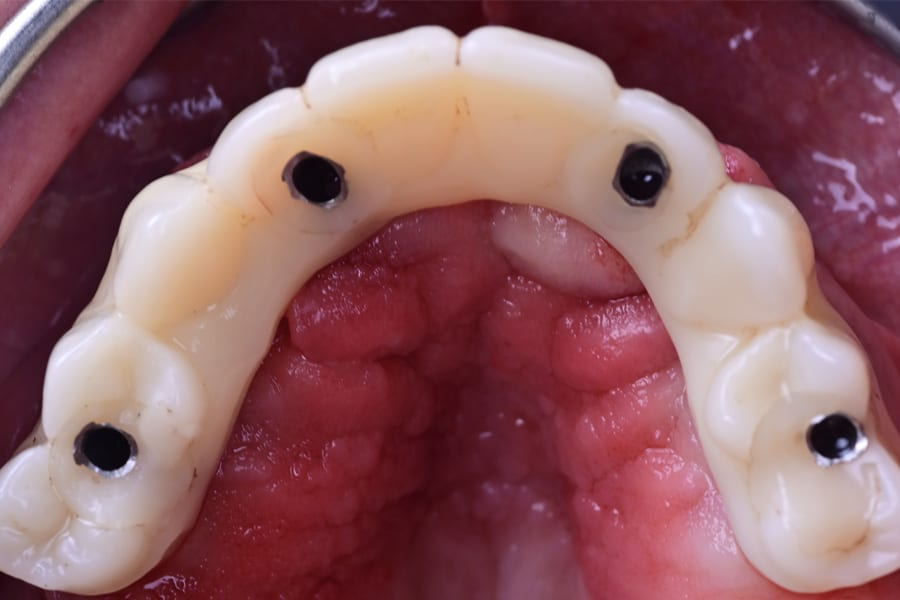

Definitive frameworks were CAD-designed and CNC-milled from titanium alloy (Figure 22). Clinical fit was confirmed with the Sheffield test (Figure 23). Monolithic zirconia superstructures were produced and vestibularly veneered with feldspathic ceramics to enhance translucency and texture (Figure 24 and Figure 25). Selective pink ceramic was applied in gingival areas requiring soft-tissue compensation (Figure 26 and Figure 27).

Occlusion was once again validated using jaw-motion tracking, confirming harmony with functional dynamics (Figure 28). The definitive prostheses were delivered as screw-retained restorations, achieving esthetic integration, functional stability, and patient satisfaction (Figure 29 and Figure 30).